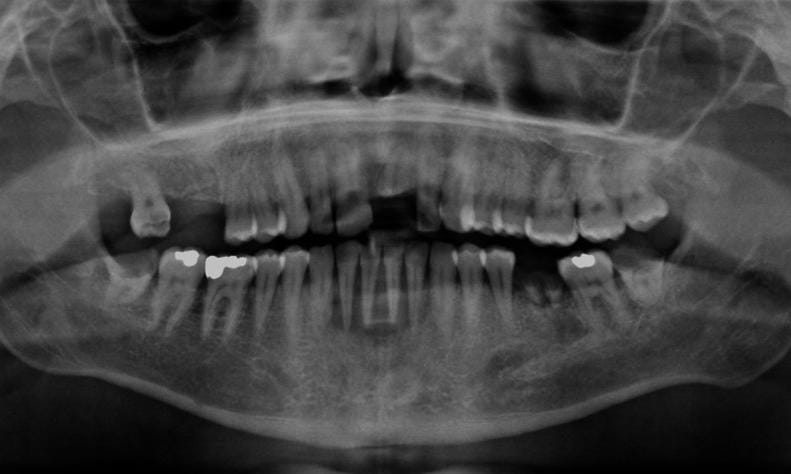

Oral cancer occurs when cells in any part of the mouth grow uncontrollably. It can occur on the lips, inside the cheeks, on the tongue, the floor or roof of the mouth, gums and even the back of the throat. What makes this cancer dangerous is that it often starts quietly as a small ulcer that r